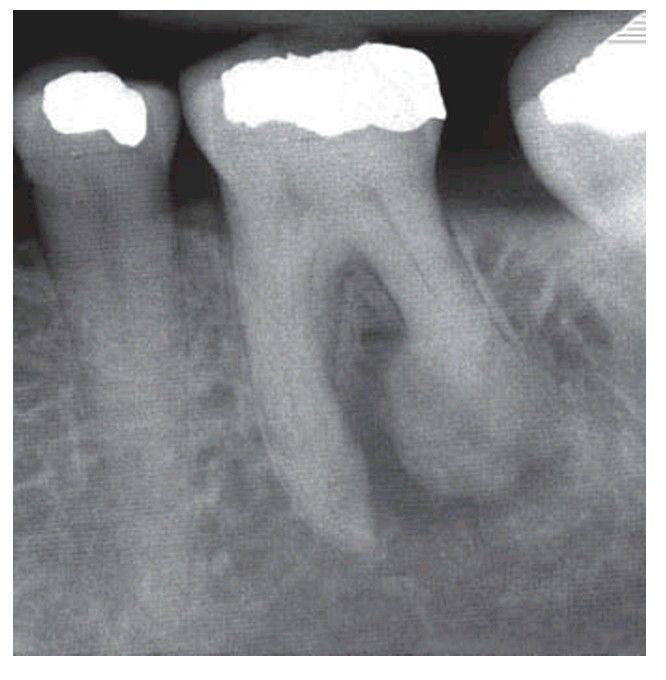

Hypercementosis as a result of apical infl ammation